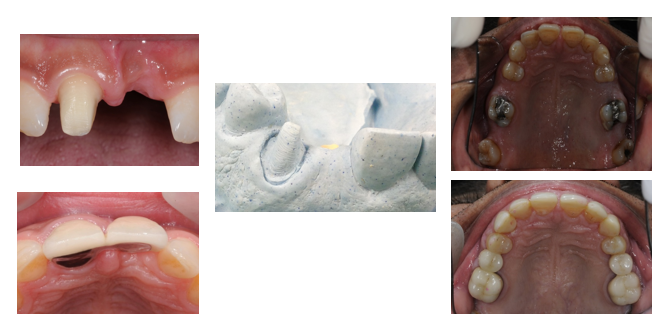

25

What is a key design feature of resin-retained bridges?

Minimal tooth preparation of abutment to maximize enamel bonding.

How should the abutment surface be prepared for resin-retained bridges?

Maximize coverage of the abutment tooth surface to maximise retention

What is a key design feature for abutment teeth in bridges?

Cover the maximal surface area of the abutment tooth.

What material and thickness should metal wing retainers have?

Rigid, non-precious metal with a thickness of 0.7(ant tooth`) -0.8mm (post tooth).

What design is recommended for adhesive bridgework in terms of pontic?

Cantilever designs with the pontics kept out of excursive contacts.

What is the clinical workflow for resin-retained bridges?

Primary impression. Diagnostic wax-up. Master impression. Bridge construction. Bridge trial and cementation.

What are design considerations for resin-retained bridges?

Light contact for the pontic in ICP. Discuss anterior wax-up with patients. Inform patients that metal wings may show through.